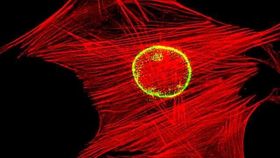

This new method has identified biomarkers that indicate a cell is truly multipotent and has not already begun to differentiate. While stem cells are typically smaller than cells that have begun to differentiate, not all of the smaller cells are stem cells. The researchers needed to identify other factors -- such as cell rigidity and the level of fluctuation within the cell's nuclear membrane -- that could be used to separate the pluripotent stems from those that are not. This method of identification will allow scientists to obtain a purer sample of MSCs for research and clinical use than have previously been used.